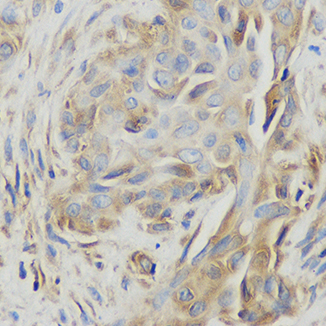

实例展示

犬脾脏免疫组化

黄病毒感染鸡肝脏

感染后鸡肝组织免疫组化图 - 合肥知恩生物

感染后鸡肝组织免疫组化图